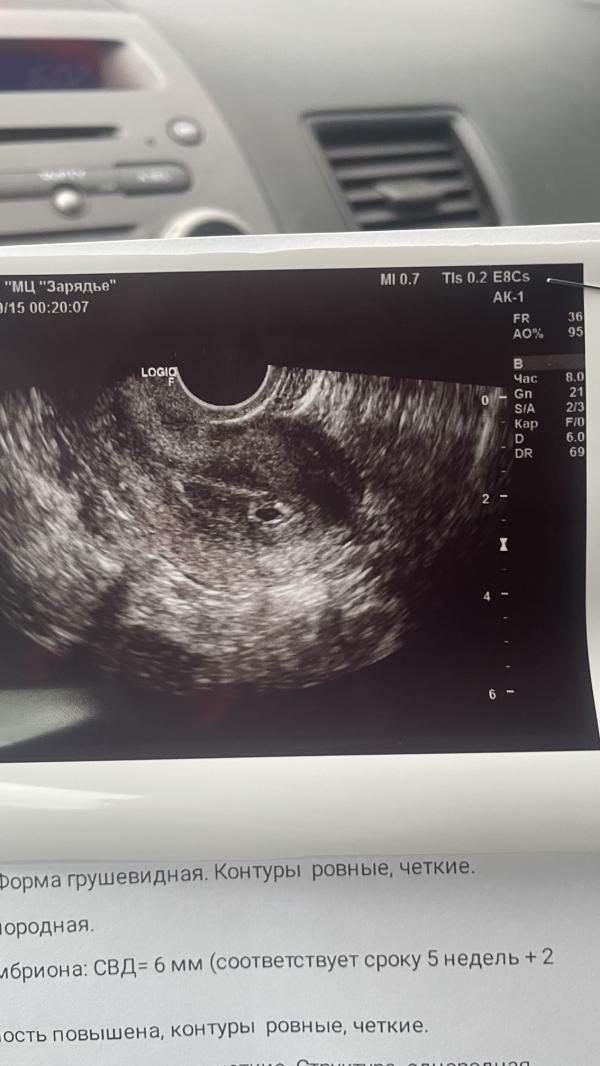

Хочу чтобы осталось здесь , напоминание что забеременеть я все таки могу 🙏🏻😌

В бой с новыми силами 🙏🏻